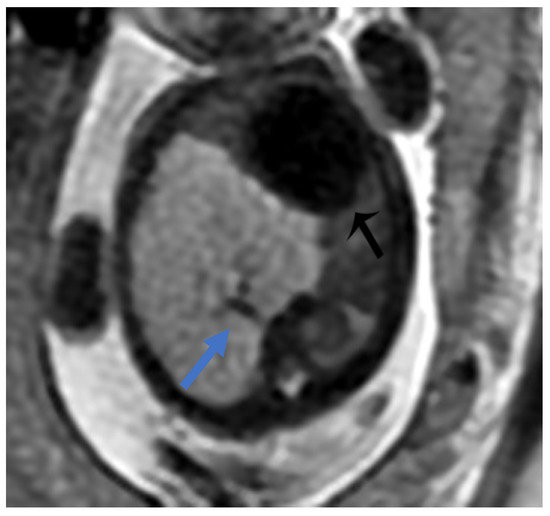

Figure 7. BPS at 27 weeks gestation. The coronal image shows a mass with higher signal intensity than the normal lung but lower signal intensity than amniotic fluid. The consolidation shifts the heart to the right (black arrow). There is a feeding artery from the aorta to suggest the diagnosis of sequestration (blue arrow).